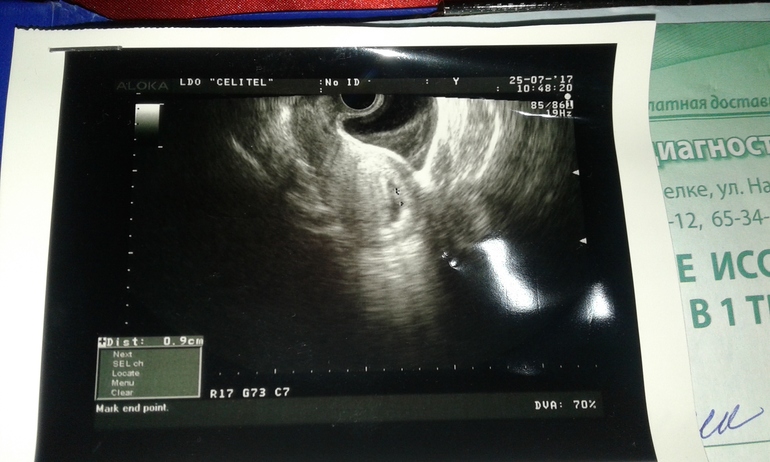

Срок Б., расчет ПДРПо акушерскому сроку шла 8-9 неделя. Пошла на узи, врач смотрела вагинально, еле касаясь делала.Видно было либо неопытная, либо малограмотная. (( определила 6 недель. Прикреплю фото, может кто поймет, опытные мамочки. По ощущениям матка слишком высоко для такого маленького срока (по узи 8-9 сейчас) а так 12! И тонус когда бывает чувствую выше лобковой кости (( не знаю что и думать ((( токс тоже вроде как отступает..

Я, честно говоря, неособо понимаю, как она там на фото Вам вывела и что хотела показать. Вот я себя сама через живот на 10-11 нед.смотрела, вроде все понятно, и померить КТР несложно.. Что ж это за врач такая Вас смотрела. Видимо по блату взяли, а опыта нет.

воот, и я о том же. Все как то размыто. . Иду к другому врачу.